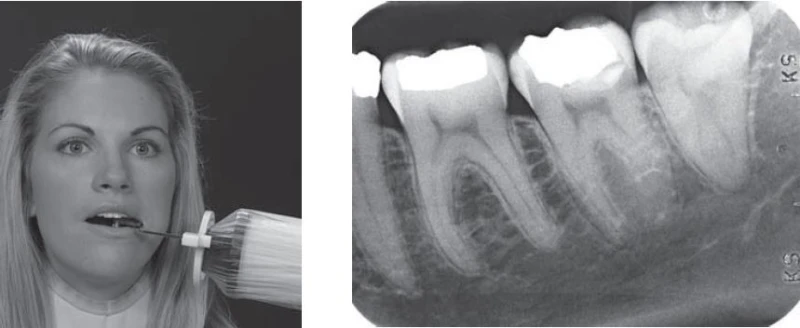

Hình 3. TIA TRUNG TÂM

Điều chỉnh góc ngang sao cho tia đi qua các vùng tiếp xúc giữa các răng. Do răng cối hơi nghiêng trong, tia trung tâm có thể có giá trị dương nhẹ (khoảng +8 độ).

Hình 4. ĐIỂM CHIẾU TIA

Điểm chiếu tia bên dưới khoé mắt ngoài khoảng 3cm trên bờ dưới xương hàm dưới.